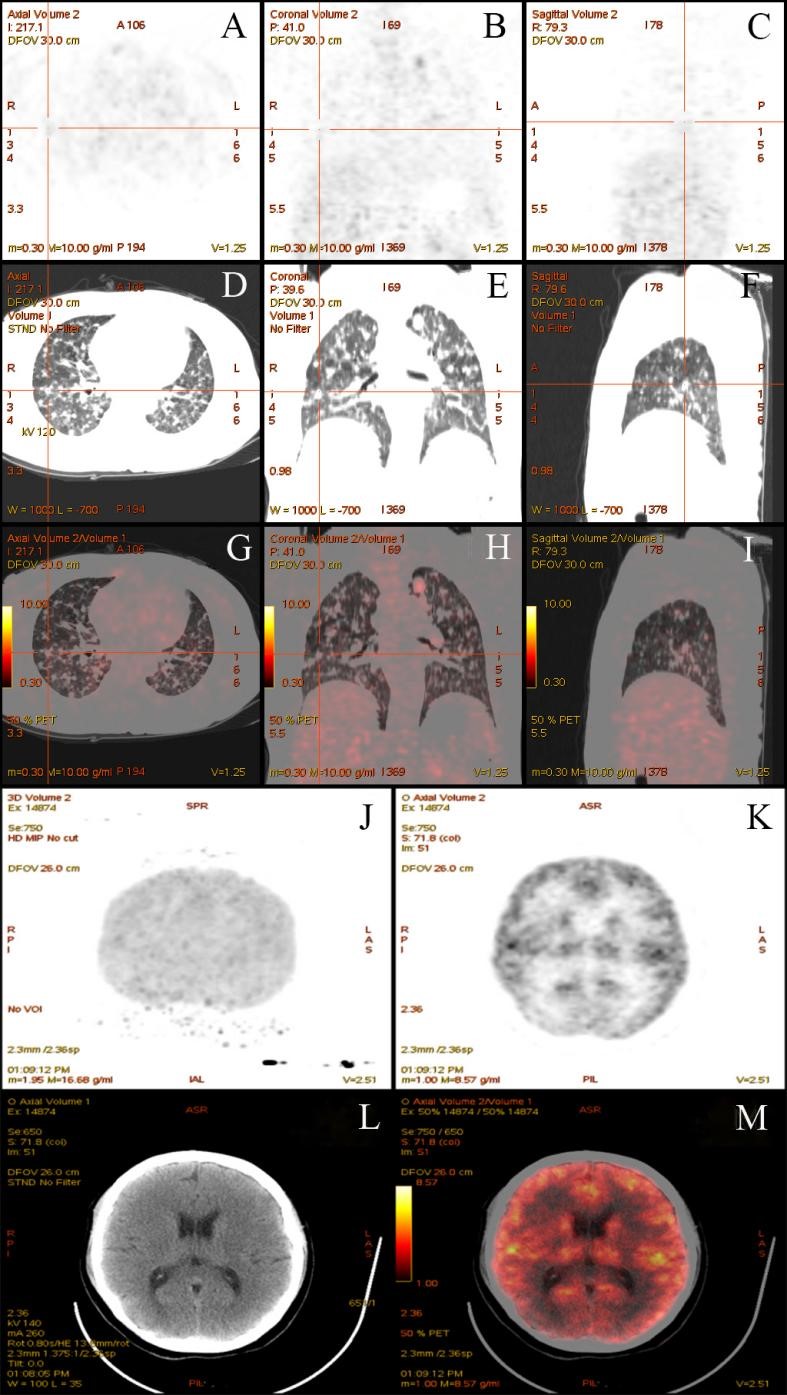

Moreover, the routine chest X-rays revealed scattered, diffuse shadows in both bilateral lungs, while a contrast-enhanced chest computed tomography (CT) scan revealed pulmonary nodules at the apex of the left lung, consistent with lung cancer with multiple double- pulmonary metastases (Figure 3). In the serum tumor markers, the carcinoembryonic antigen is elevated to 19.19 ng/ml, and the carbohydrate antigen 153 is elevated to 69.99 U/ml. Positron emission tomography-CT (PET-CT), a more sensitive tool for detecting meningeal dissemination, confirmed diffuse malignant lesions in the lung, with suspected lymphatic metastasis involving the left supraclavicular, inferior thoracic, and mediastinal lymph nodes. No abnormalities were found in other regions (Figure 4). A biopsy of the left supraclavicular lymph nodes revealed invasive adenocarcinoma cells (Figure 5).

Figure 4 Positron emission tomography-CT (PET-CT)

The PET-CT prompted the diffuse and varied size malignant lesions of lung (A to I) and revealed nothing remarkable in the meninges, brain parenchyma and brain ventricles ( J to M).